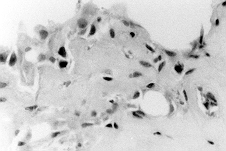

Higher magnification of the epithelium lining the cavity.